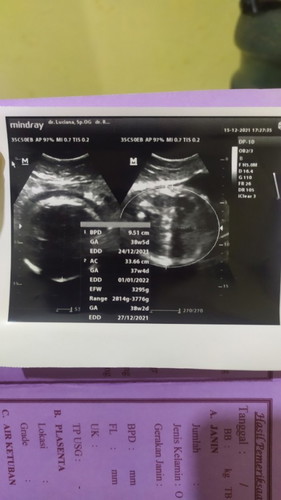

Bun aku awal hamil itu udh di kasih tau sama bidan kalau hpl aku 15januari . Trs kmaren aku USG di usia 35-36week kok hpl nya maju ya. Tertera di hasil USG hpl antara 24des 27des dan 1jan. Bidan ku sampai bingung. Kok maju nya banyak sekali. Dan juga bb baby aku drastis naiknya. Terakhir USG masih 2.1kg lalu 2minggu lagi USG kok bb nya udah 3.3kg aja. Apa mungkin karna bb baby yang besar jadi hpl ku maju ya bun? Mohon sarannya#seriusnanya #bantusharing #ingintahu #pleasehelp